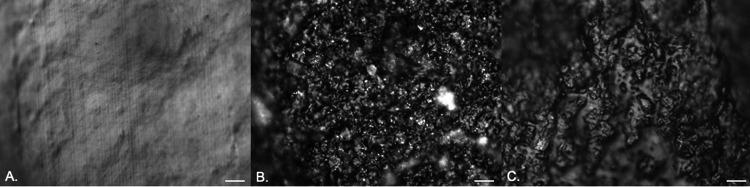

Catheter-associated urinary tract infections have serious consequences, for both patients and health care resources. Much work has been carried out to develop an antimicrobial catheter. Although such developments have shown promise under laboratory conditions, none have demonstrated a clear advantage in clinical trials. Using a range of microbiological and advanced microscopy techniques, a detailed laboratory study comparing biofilm development on silicone, hydrogel latex, and silver alloy-coated hydrogel latex catheters was carried out. Biofilm development by , , and on three commercially available catheters was tracked over time. Samples were examined with episcopic differential interference contrast (EDIC) microscopy, culture analysis, and staining techniques to quantify viable but nonculturable (VBNC) bacteria. Both qualitative and quantitative assessments found biofilms to develop rapidly on all three materials. EDIC microscopy revealed the rough surface topography of the materials. Differences between culture counts and quantification of total and dead cells demonstrated the presence of VBNC populations, where bacteria retain viability but are not metabolically active. The use of nonculture-based techniques showed the development of widespread VBNC populations. These VBNC populations were more evident on silver alloy-coated hydrogel latex catheters, indicating a bacteriostatic effect at best. The laboratory tests reported here, which detect VBNC bacteria, allow more rigorous assessment of antimicrobial catheters, explaining why there is often minimal benefit to patients. Several antimicrobial urinary catheter materials have been developed, but, although laboratory studies may show a benefit, none have significantly improved clinical outcomes. The use of poorly designed laboratory testing and lack of consideration of the impact of VBNC populations may be responsible. While the presence of VBNC populations is becoming more widely reported, there remains a lack of understanding of the clinical impact or influence of exposure to antimicrobial products. This is the first study to investigate the impact of antimicrobial surface materials and the appearance of VBNC populations. This demonstrates how improved testing is needed before clinical trials are initiated.

导管相关尿路感染会对患者和医疗资源造成严重后果。为了开发抗菌导管,已经开展了大量工作。尽管这些研究在实验室条件下显示出了一定的前景,但在临床试验中没有一项研究显示出明显的优势。本研究使用一系列微生物学和先进显微镜技术,对硅胶、水凝胶乳胶和银合金涂层水凝胶乳胶导管上生物膜形成进行了详细的实验室比较研究。通过时间追踪,研究了 在三种市售导管上的生物膜形成情况。使用相差微分干涉对比(EDIC)显微镜、培养分析和染色技术对样本进行检查,以量化活但非可培养(VBNC)细菌。定性和定量评估都发现生物膜在所有三种材料上都迅速形成。EDIC 显微镜揭示了材料粗糙的表面形貌。培养计数和总细胞及死亡细胞定量之间的差异表明存在 VBNC 群体,这些细菌仍具有活力但无代谢活性。非培养技术的使用显示出广泛的 VBNC 群体的发展。在银合金涂层水凝胶乳胶导管上,VBNC 群体更为明显,这表明最好是具有抑菌作用。这里报告的实验室测试可以检测 VBNC 细菌,从而更严格地评估抗菌导管,这解释了为什么对患者的益处通常很小。已经开发了几种抗菌导尿管材料,但尽管实验室研究可能显示出益处,但没有一种显著改善了临床结果。使用设计不佳的实验室测试且没有考虑 VBNC 群体的影响可能是原因之一。虽然 VBNC 群体的存在报告越来越多,但对其临床影响或接触抗菌产品的影响仍缺乏了解。这是第一项研究抗菌表面材料和 VBNC 群体出现的影响的研究。这表明在启动临床试验之前,需要进行改进的测试。